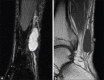

Magnetic Resonance Imaging Appearance of Schwannomas from Head to Toe: A Pictorial Review

Schwannomas are benign soft-tissue tumors that arise from peripheral nerve sheaths throughout the body and are commonly encountered in patients with neurofibromatosis Type 2. The vast majority of schwannomas are benign, with rare cases of malignant transformation reported. In this pictorial review, we discuss the magnetic resonance imaging (MRI) appearance of schwannomas by demonstrating a collection of tumors from different parts of the body that exhibit similar MRI characteristics. We review strategies to distinguish schwannomas from malignant soft-tissue tumors while exploring the anatomic and histologic origins of these tumors to discuss how this correlates with their imaging findings. Familiarity with the MRI appearance of schwannomas can help aid in the differential diagnosis of soft-tissue masses, especially in unexpected locations.